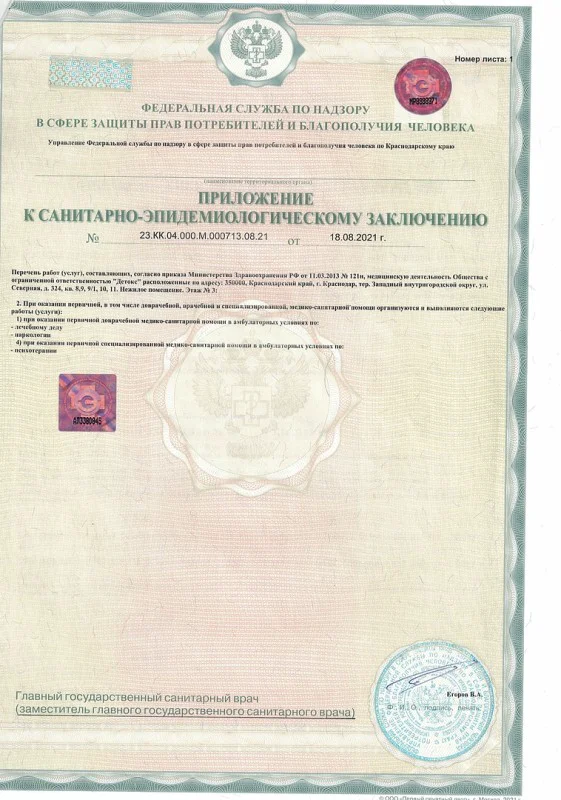

Лицензия на осуществление медицинской деятельности

Лицензия на осуществление медицинской деятельности

Лицензия на осуществление медицинской деятельности

Лицензия на осуществление медицинской деятельности

Лицензия на осуществление медицинской деятельности

Лицензия на осуществление медицинской деятельности

Лицензия на осуществление медицинской деятельности

Лицензия на осуществление медицинской деятельности